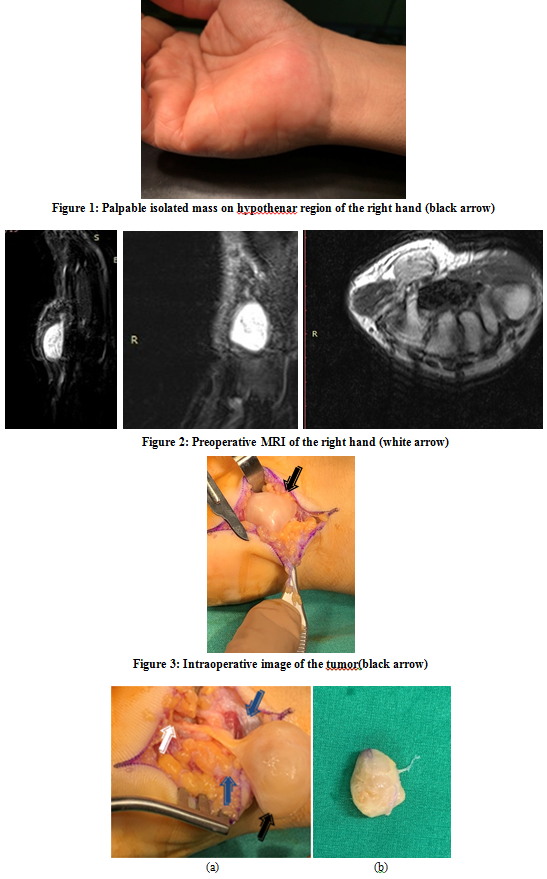

Open AccessCase Report

Solitary Schwannoma on the Hypothenar Region of the Hand: A Literature Review

Kastanis G, Kapsetakis P, Magarakis G, Bachlitzanaki M, Christoforidis C, Kazamias G, Pantouvaki A

International Journal of Innovative Research in Medical Science·October 4, 2020